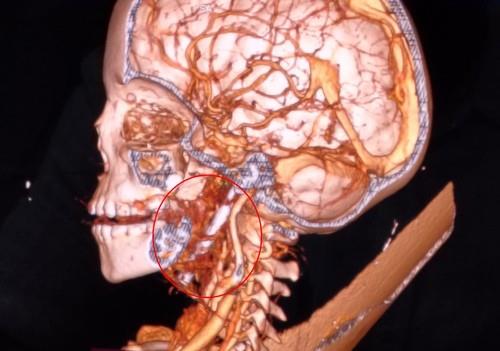

Dečaku se tokom igranja ekser od 8 cm zabio u glavu: Lekari se smrznuli kad su videli snimak, ono što je potom usledilo je čudo (FOTO)

dečak ekser profimedia-1005204028.jpg

1 / 4

TIM / Jam Press / Profimedia